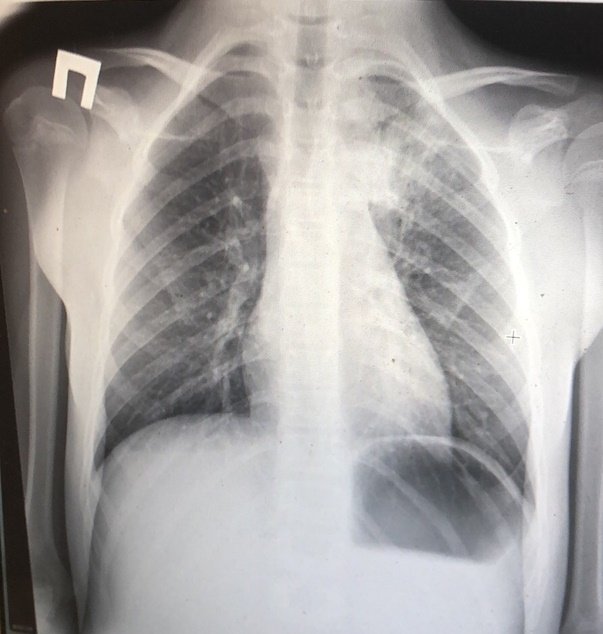

При пневмонии, на рентгеновском снимке легких, видны следующие признаки:

- в разных частях органа находятся очаги затемнения, имеющие неровные контуры и размер 3-12 мм;

- различаются тени по внешнему виду (овальные, кольцевидные, круглые), интенсивности цвета – чем темнее будет пятно, тем сильнее патологический процесс;

- если поражены лимфатические узлы и нарушено кровоснабжение органа, может быть заметно изменение корней лёгких, если поражена плевра – видны нарушения в рисунке куполов диафрагмы.

На рентгеновском снимке пневмония выглядит следующим образом: